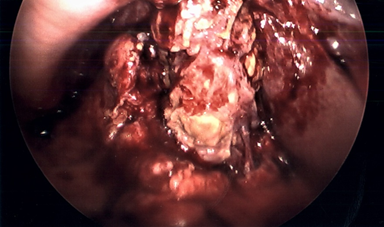

Patient was readmitted about 6 weeks later with acute changes in mental status, secondary to acute aspiration pneumonia. He developed bilateral pleural effusions and had a right-sided thoracocentesis performed. Around this time, his IR cholecystostomy drain fell out, and his liver function tests started to trend up - suggestive of ongoing acute on chronic cholecystitis. He underwent an ultrasound scan at this time which failed to visualize the gallbladder due to extensive distention of bowel gas shadows. Hence IR could not reposition the percutaneous drain. He was therefore taken to the operating room for planned laparoscopic cholecystectomy, after his acute medical condition was stabilized. Intraoperatively, there were extensive dense adhesions around the gallbladder. The gallbladder itself appeared thickened, contracted and was very friable (Figure 1). Attempt to dissect the cystic duct and cystic artery was deemed unsafe due to the significant adhesions and poor tissue friability. Hence decided to perform LCtube placement. A 12 French Foley catheter was inserted through one of the 5 mm port sites and placed into the fundus of the gallbladder. The balloon was then inflated within the gallbladder to secure it in place (Figure 2). A Jackson Pratt (JP) drain was inserted adjacent to it in the gallbladder fossa.

Figure 2 Laparoscopic cholecystostomy tube.